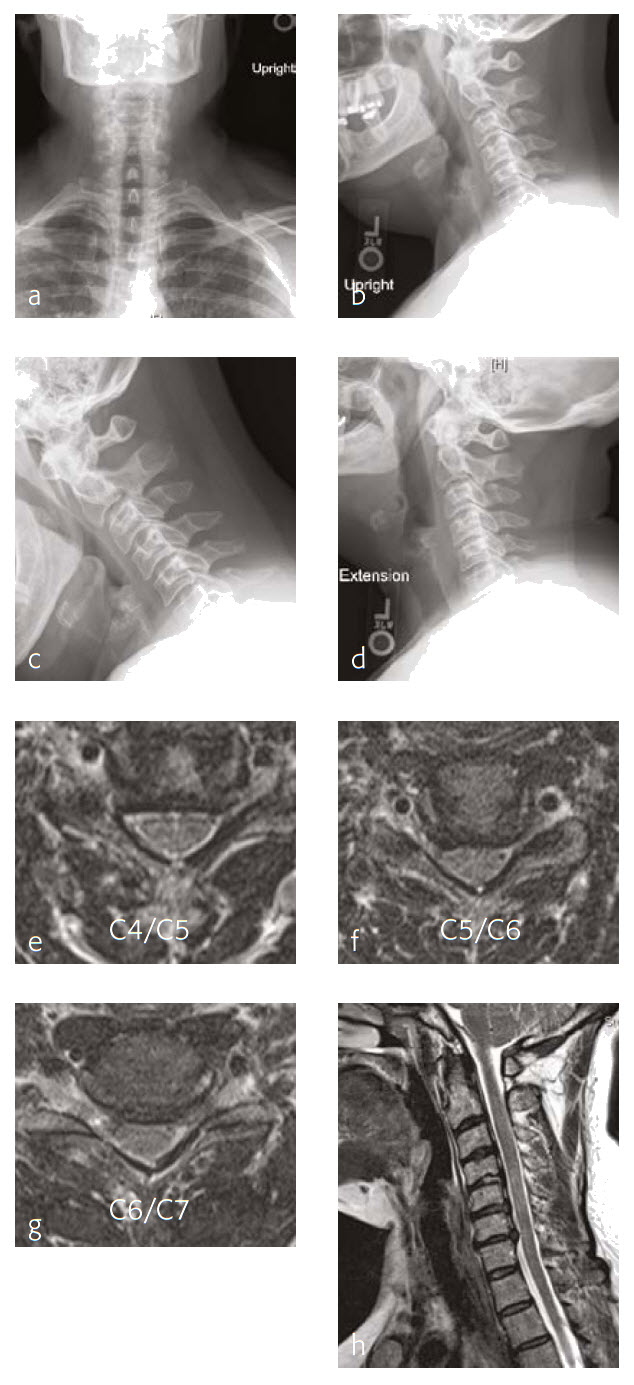

A 56-year-old man, partly left-hand dominant partly right-hand dominant depending on the activity, presented with progressive left shoulder and arm weakness with pain radiating from his neck down to his left shoulder and an EMG documenting a left C5 radiculopathy (Fig 1).

The patient claimed a normal state of health until 5 weeks previous. This then began to backtrack to the neck and to develop weakness in his left arm to the biceps and deltoid. On examination, the patient had 4/5 deltoid and biceps strength on the left and decreased sensation along his lateral shoulder.

The patient showed normal lordosis in his extension x-rays. He has approximately 2 mm of anterolisthesis of C4 on C5 in his extension on his flexion x-ray. This increases to approximately 56 mm and persists in his normal upright film with again some component of spondylolisthesis at that level.

The patient's earlier MRI shows severe left-sided C4-C5 foraminal stenosis and multilevel disc degeneration with very mild central narrowing at C3-C4, C6- C7, and C7-T1. He also has a small right paracentral disc herniation at C6-C7.

The new MRI of the C4-C5 showed mild uncovering of the disc posteriorly due to grade 1 anterolisthesis. There is also mild left facet arthropathy with left uncovertebral joint osteophytes resulting in moderate left neural foraminal narrowing. The right neural foramen is adequately patent.

Follow-up (4 months)

At the patient follow-up at 4 months postoperative, he described complete resolution of left upper extremity pain (Fig 2). He was also happy with his left upper extremity strength and was extremely pleased with his progress. He continued to have no left upper extremity pain. He also believed that he had made significant progress in terms of his left upper extremity range-of-motion and strength.